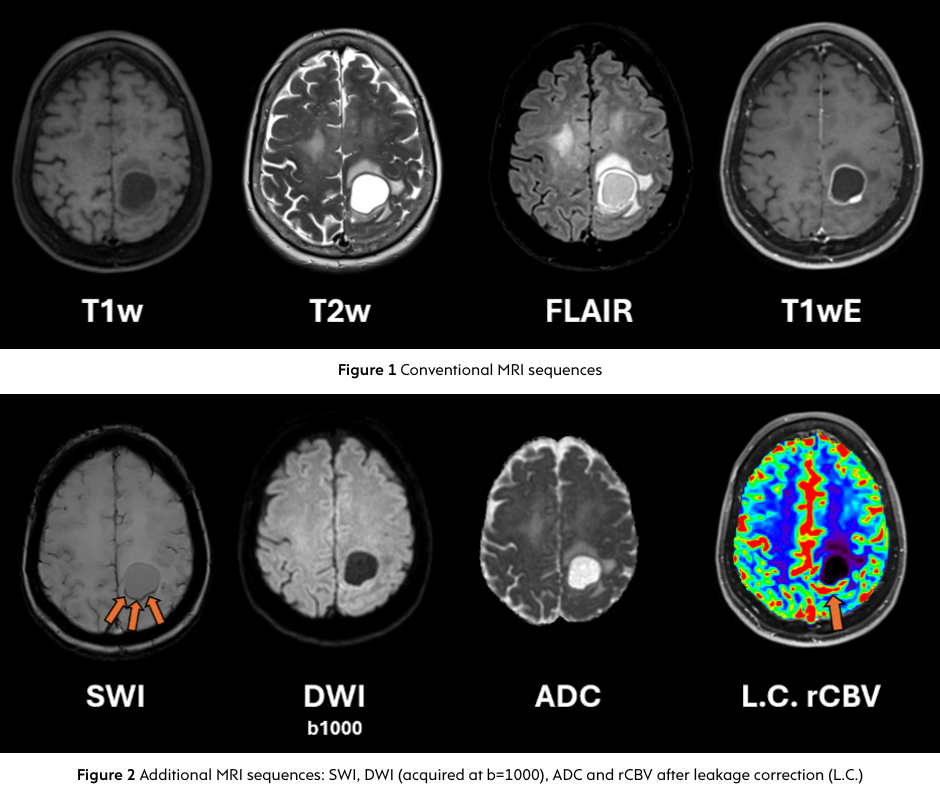

Durch die Kombination modernster magnetischer Markierung des Blutflusses mit präziser mathematischer Modellierung erzeugt pCASL hochauflösende Perfusionskarten und liefert quantitative Messungen des zerebralen Blutflusses. Solche genauen Daten sind entscheidend bei der Diagnose und Behandlung neurologischer Erkrankungen wie Schlaganfällen, Demenz oder Hirntumoren.

Ob Ischämie bei Schlaganfall, Perfusionsveränderungen bei Alzheimer oder Überwachung von Hirntumoren